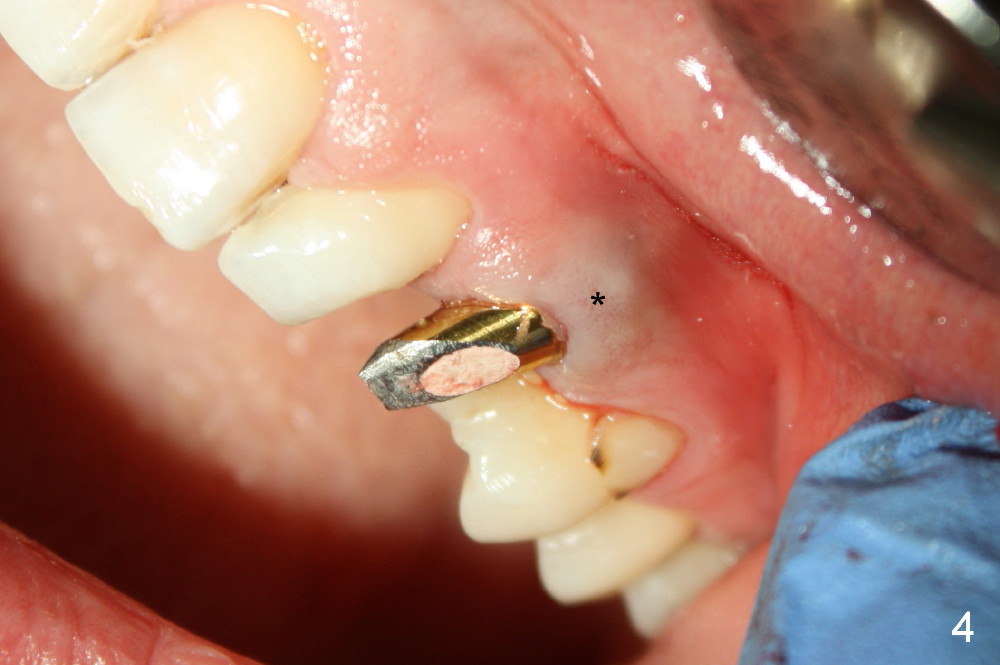

The 42-year-old lady refuses to take antibiotic prior to surgery due to lactation. The extraction of the upper left deciduous canine is not difficult as expected. There appears to be no granulation tissue. What is unexpected is difficulty in osteotomy. Initial osteotomy is too palatal, apparently perforating the palatal plate. The osteotomy has to be changed: slightly palatal to the center of the original socket (Fig.1: 2 mm pilot drill). As drills increase in diameter, the coronal end of the drills have to be tilted buccally, because it feels like that the labial plate at the apical end is going to be perforated. When 4.5x14 mm bone level implant is placed, the implant is sticking out too much (Fig.2). To alleviate this cosmetic issue, the implant is placed deeper (Fig.3). A 25º angled abutment is placed with heavy labial reduction (Fig.4,5). The patient is pleased with a stable new tooth, but the operator is not (Fig.6). Removal of the implant may be not the wildest guess. Two or three days postop, the patient reports pain and swelling. The symptoms disappears after antibiotic. One week follow up reveals wound healing normal. The gingiva returns to its normal color, as compared to purplish appearance in Fig.4,6 (immediately postop). In fact, the implant fails in a month.